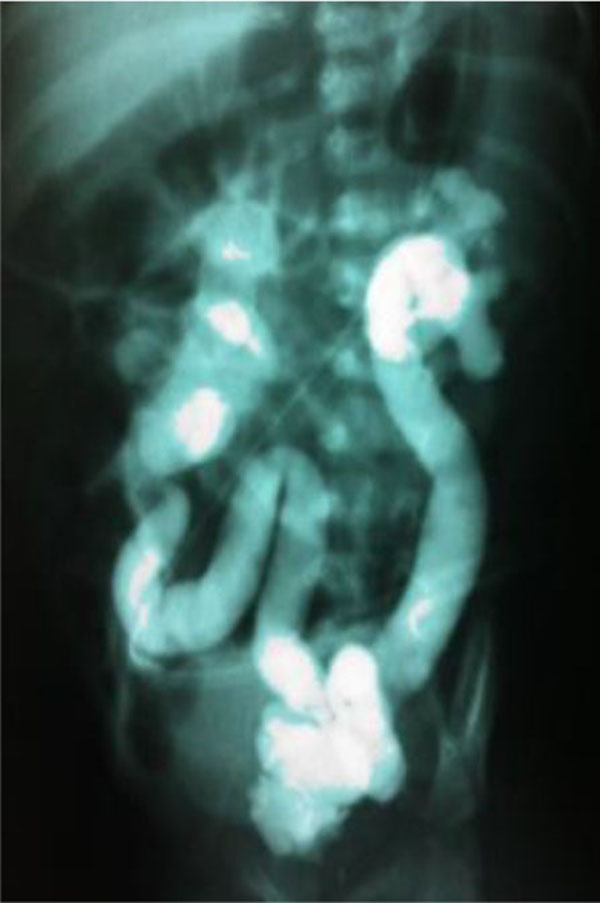

The family under study was constituted of 3 siblings (Fig. 1). The older sister refused to have blood samples collected and consequently she was not included in the genomic analysis. All family members, except the proband, had normal renal function and normal kidney and urinary tract anatomy. The twins, born in 22/08/2008 at 38 ± 1 weeks of gestation, were monozygotic, monochorionic and diamniotic. The first signs of CAKUT in the proband were seen during the US screening at 29 ± 1 weeks of gestation when his fetal biometry revealed left kidney ectasy and an increase bladder volume. In a spite of these prenatal US findings, the proband was not primarily referred for further investigations or treatment. A retrospective evaluation of pregnancy history did not identify exposure to known environmental risk factors for fetal anomalies. During his first month of life, in 19/09/2008, the proband developed urinary tract infection followed by sepsis and acute renal failure. He was then hospitalized in an intensive care unit and started peritoneal dialysis. Interruption of the dialysis sessions occurred after infection control and partial recovery of the renal function. During the hospital stay, a miccional urethrocystography revealed bilateral megaureter associated with grade V vesicoureteral reflux, as shown in (Fig. 2). In 13/10/2008, the proband underwent bilateral surgical re-implant of the ureters and was then referred to outpatient care at the Pediatric Nephrology Unit. At the time of recruitment, the two monozygotic twins were five years old and the proband exhibited CKD stage III.